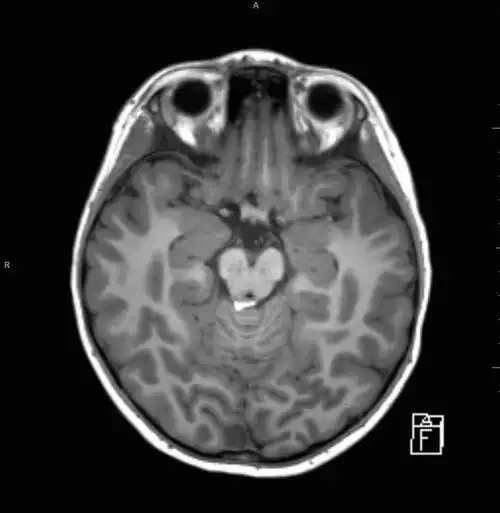

颅内脂肪瘤

颅内脂肪瘤一例

脑子进「脂肪」了:小儿颅内脂肪瘤一例